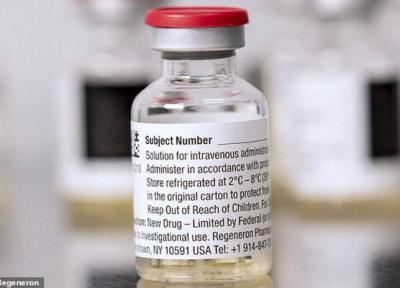

این دارو 100 درصد کرونا را از بین می برد؟

دانشمندان انگلیسی دارویی را ساخته اند که مدعی هستند این دارو به طور 100 درصد از پیشرفت ویروس کووید-19 در بدن جلوگیری می کند.